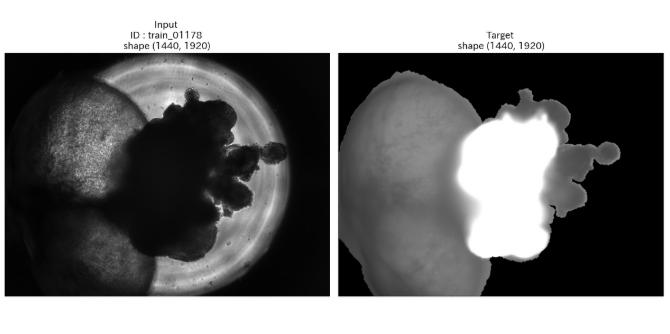

通常、顕微鏡で細胞の構造を詳しく観察するためには、特殊な薬品で色をつける「染色」という工程が必要です。しかし、これには手間やコストがかかるだけでなく、薬品によって細胞そのものが変化してしまうという課題がありました。今回のコンテストでは、AIを用いて染色していない画像から染色した後の状態を予測・生成する「仮想染色」の精度が競われました。野田助教らのチーム「AcademiX Medical」は、エンジニアと医師の知見を融合させ、極めて精度の高いAIモデルを構築。染色なしでも細胞の詳細な情報を得られる可能性を示し、全80チーム中、第2位という高い評価を獲得しました。